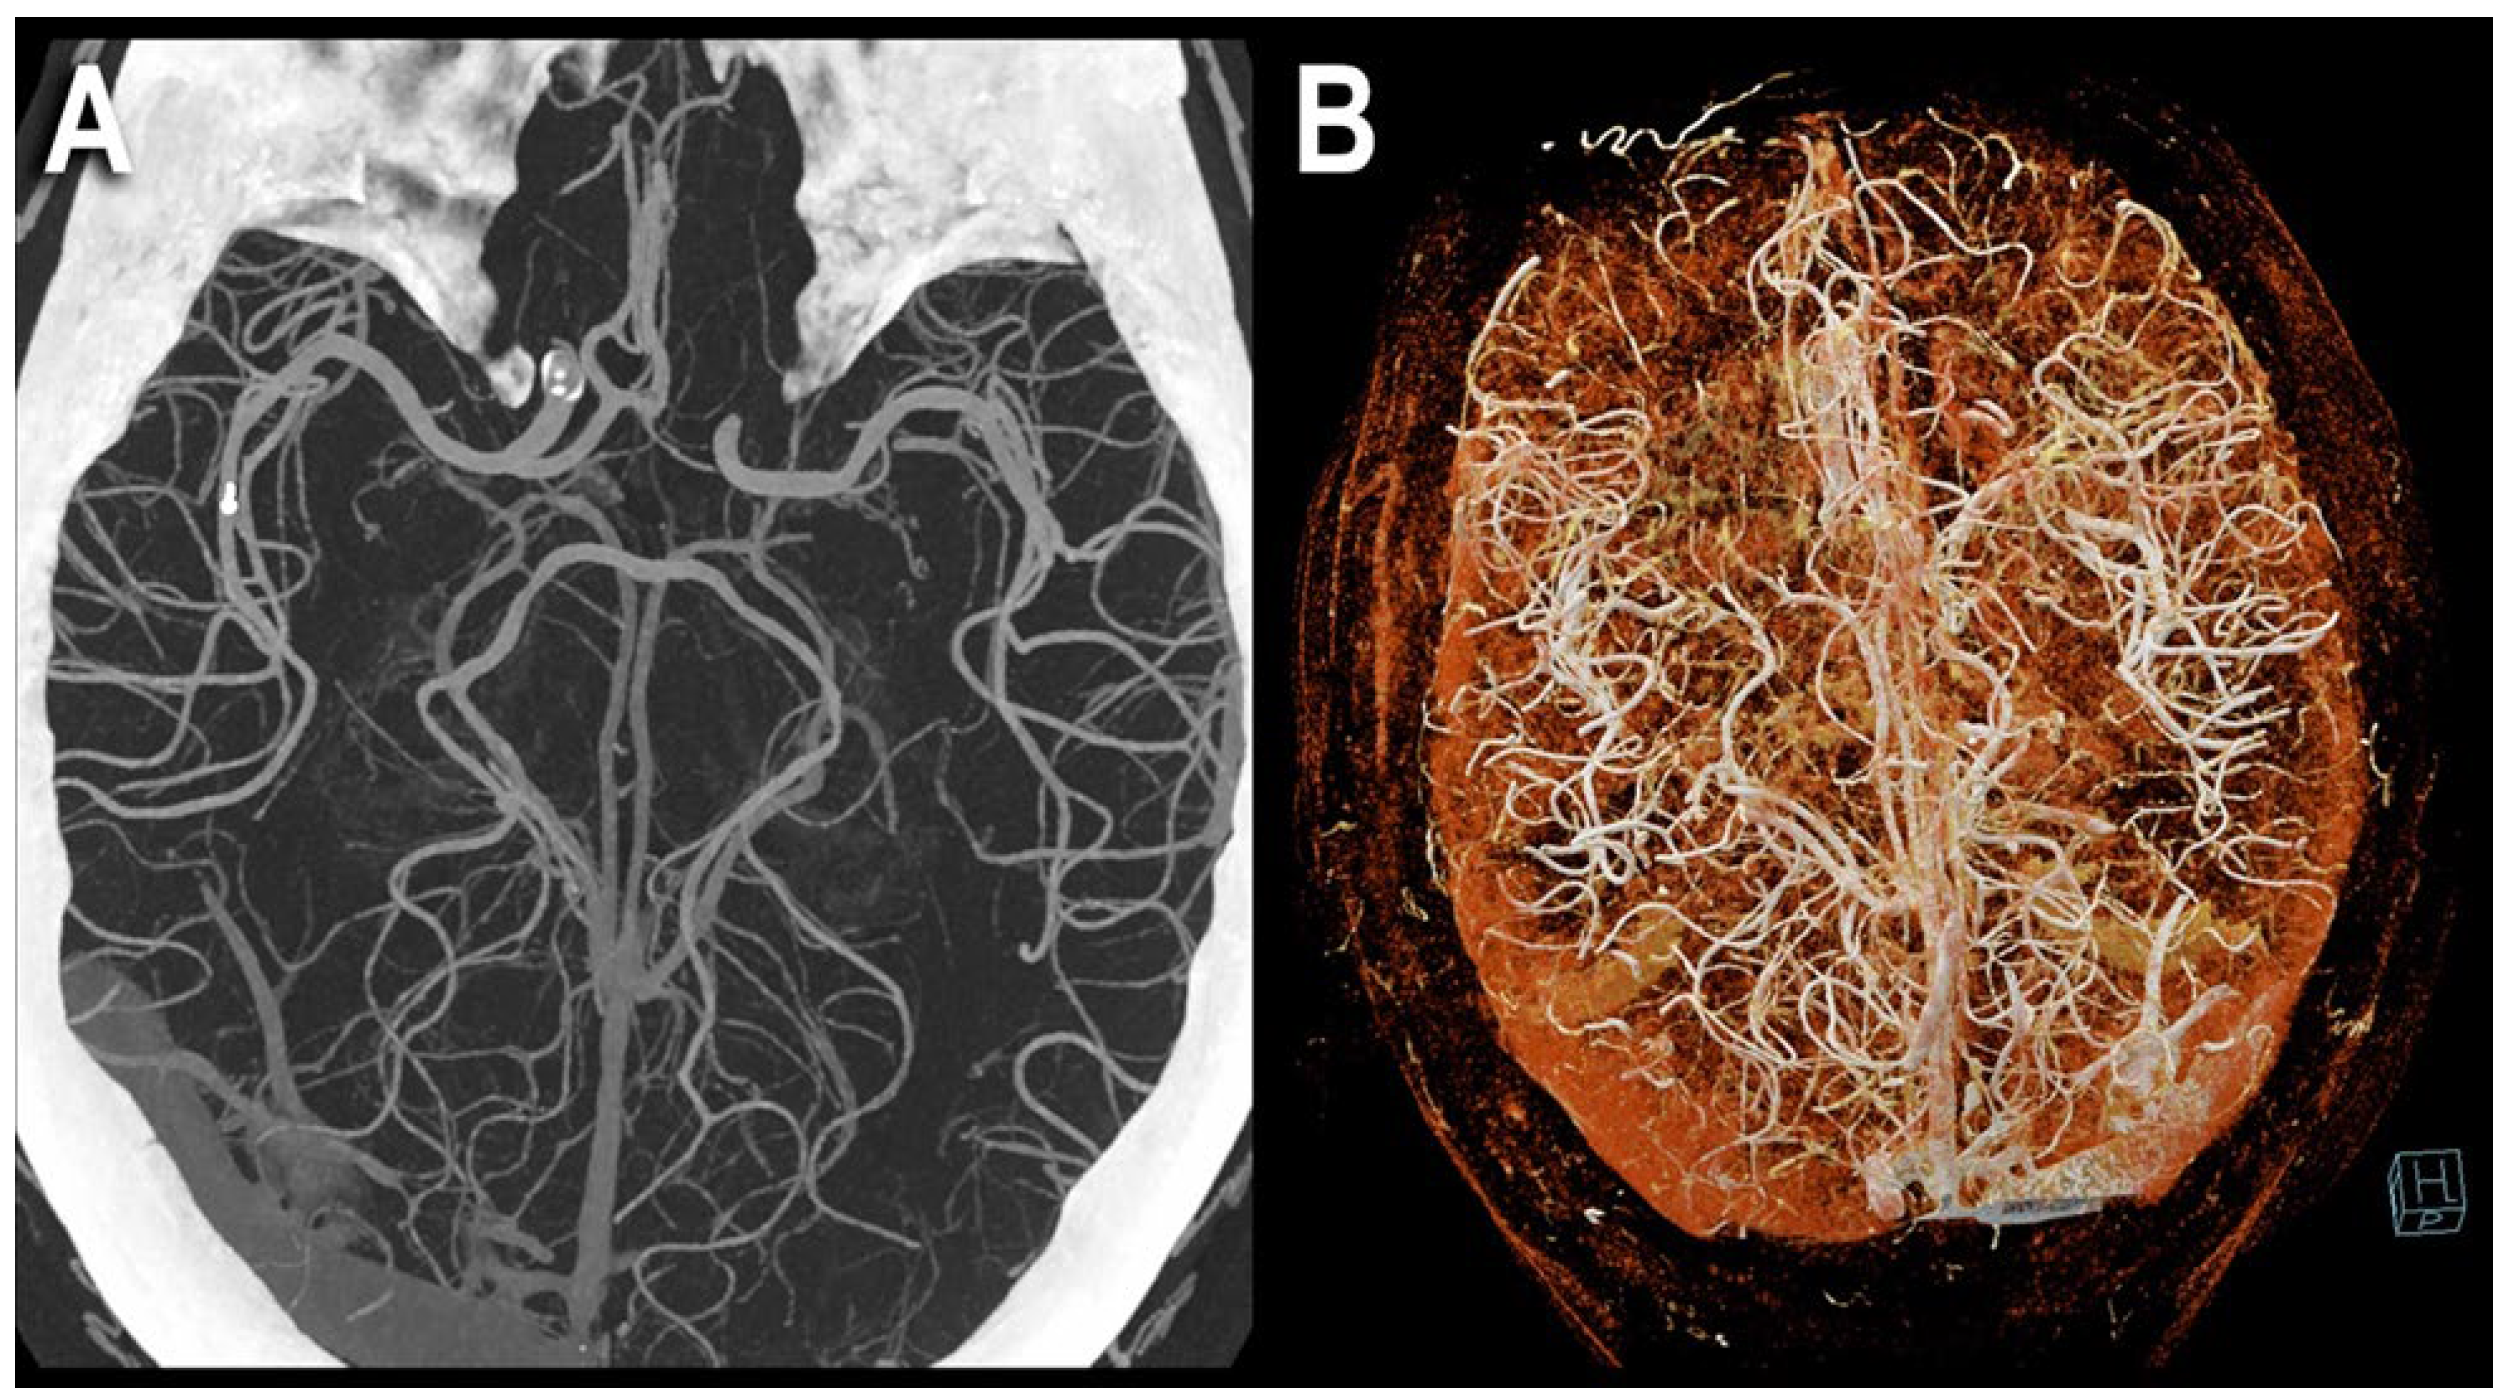

6.3. Increased Resolution

- Michael, A.E.; Boriesosdick, J.; Schoenbeck, D.; Lopez-Schmidt, I.; Kroeger, J.R.; Moenninghoff, C.; Horstmeier, S.; Pennig, L.; Borggrefe, J.; Niehoff, J.H. Photon Counting CT Angiography of the Head and Neck: Image Quality Assessment of Polyenergetic and Virtual Monoenergetic Reconstructions. Diagnostics 2022, 12, 1306. [Google Scholar] [CrossRef]

| Michael et al. [28] | 2022 | In vivo (human) | 37 | Iodine-only images | The most favorable contrast-to-noise-ratio and signal-to-noise-ratio were detected in the PER and low keV MER. In the qualitative image analysis, the PER was superior to the MER in all rated criteria. For MER, 60–65 keV was rated as best image quality. |